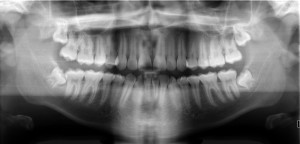

You may be required to have a sinus augmentation if a CT scan or x-ray shows that there is an insufficient amount of bone in your upper jaw to properly support dental implants.

First

, your dentist will take a CT scan of your jaw. This will provide a clear 3D image of the sinus cavity and jawbone, enabling your dentist to plan the surgical procedure in detail.